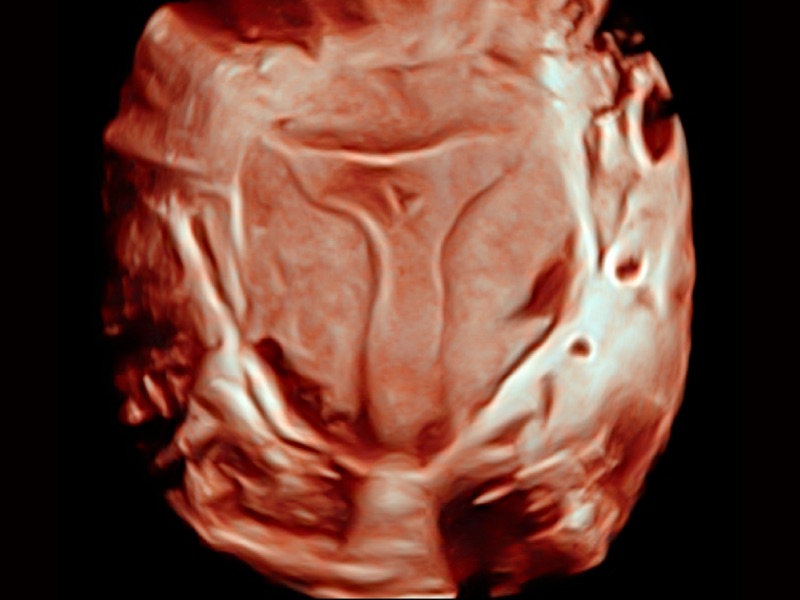

三维光影成像技术采用新型的渲染方式,增强边缘信息,使得轮显示清晰完整,为临床提供丰富、直观的三维结构,提供临床诊断准确性。